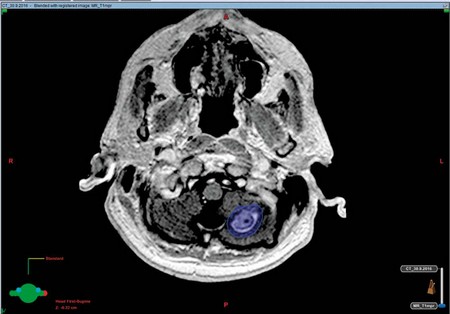

Mezitím ovšem začíná další část procesu pro lékaře radioterapeuta – zakreslení kontur cílových objemů a kritických struktur do plánovacích CT snímků, jejich fúzování s MR pro lepší orientaci a rozlišení v měkkých strukturách (obr. 8, 9).

Obr. 8, 9 – Fúze snímků plánovacího CT a MR vyšetření